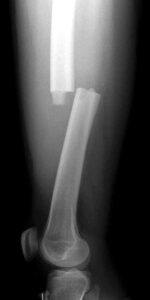

- X-rays: The primary method for assessing fractures, X-rays offer clear images of dense structures, such as bones. They reveal whether the bone is intact or broken, the fracture type, and its exact location within the femur.

X-ray shows a transverse fracture of the femur. The break is a straight horizontal line across the shaft.